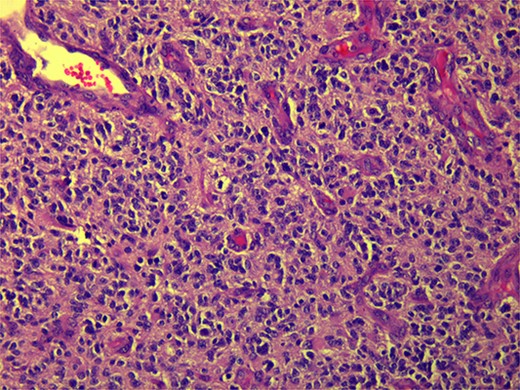

A 59-year-old female patient, married with no offspring. Surgical history includes cholecystectomy (2017). Her brother died due to lymphoma; otherwise, there is no family history of cancer. She presented complaining of chronic constipation, weight loss, abdominal distention, and perianal pain. Colonoscopy revealed a 5-cm mass extended from the anus. Biopsy revealed invasive, moderately differentiated rectal adenocarcinoma (Fig. 1).

Microscopic view (×10) of pathology slide of colorectal cancer.